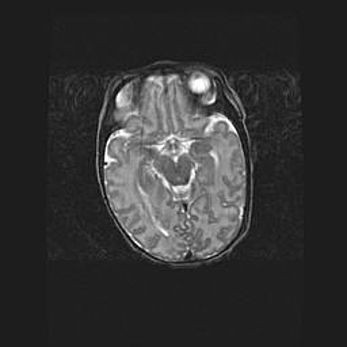

Множественные кисты обоих полушарий головного мозга, наибольшая из них в правой затылочной области. Ассиметричная атрофическая гидроцефалия.

Возраст: 7 месяцев

Вес: 5660 г

Пол: мужской

Окружность головы: 41,5 см

Срок гестации: 28-29 недель

Кисты головного мозга развиваются в результате многоочаговых некрозов вещества мозга и возникают вследствие перенесенной перинатальной инфекции, менингитов, энцефалитов, асфиксии, родовой травмы, расстройств мозгового кровообращения различного генеза. Образованию кист в веществе головного мозга плодов и новорожденных способствуют такие факторы, как высокое содержание в нем воды, недостаточная (или отсутствие) миелинизация и слабая астроглиальная реакция на повреждение.

Кисты могут сочетаться с гидроцефалией и другими поражениями головного мозга.